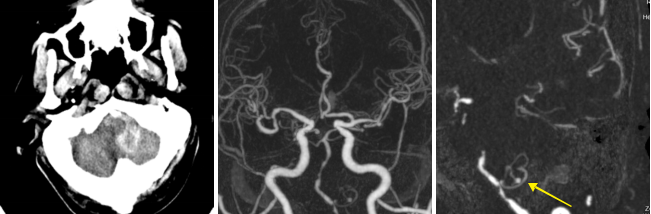

病例三 男,66歲, 突發(fā)頭痛30分鐘, 顱內(nèi)多發(fā)小動(dòng)脈瘤。

CT平掃可見(jiàn)顱內(nèi)左側(cè)小腦區(qū)有環(huán)形高密度影,CTA- MIP中顯示左小腦后下動(dòng)脈瘤, 直徑 約3 mm(黃箭頭所指)

VR圖像中清晰可見(jiàn)前交通動(dòng)脈處小動(dòng)脈瘤1直徑約2mm(紅箭頭所指)

有文章指出, 減影容積CT血管成像對(duì)于檢測(cè)腦動(dòng)脈瘤(3 - 8 mm)的敏感性: 大于8毫米為95 . 6 %左右, 而對(duì)于小于3毫米的微動(dòng)脈瘤卻很容易漏診。

640層寬體探測(cè)器CT擁有0 . 5 mm層厚的探測(cè)器單元, 對(duì)于細(xì)小的病變能夠清晰顯示,大大提高了對(duì)微動(dòng)脈瘤的檢出率。